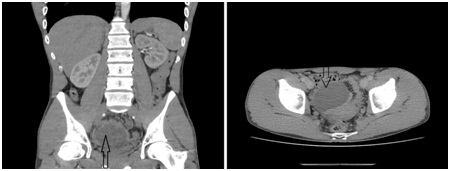

A computed tomography (CT) Scan of the abdomen with intravenous contrast was ordered. A deep pelvic intraperitoneal cystic lesion about 6.5x5.5 cm is noted in the RLQ, abutting the urinary bladder superiorly without involvement of the major vessels (Figures 1). No lymphadenopathy, or other visible masses were recorded.

Figure 1: A computed tomography scan of the abdomen and pelvis showing a huge exophytic, 6.5x5.5 cm intrapelvic mass, abutting the urinary bladder (black arrow).